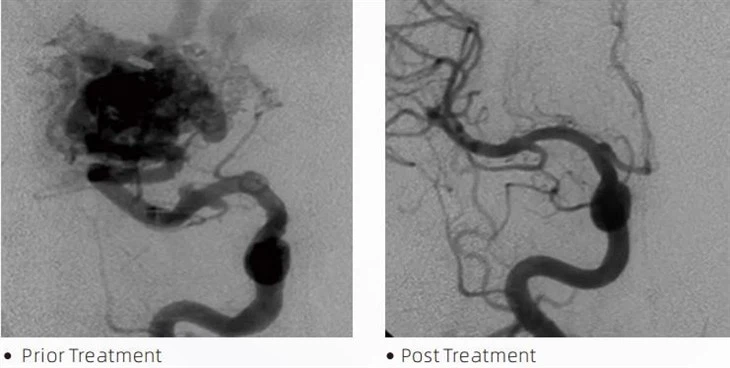

The Lava liquid embolic agents in interventional radiology is used in a variety of interventional radiology procedures. Lava liquid embolic agents are used to fill the abnormal vessels and stop the blood flow, effectively treating the AVM and hypervascular in the brain. AVMs can be treated with liquid embolic agents by injecting the substance into the vessels that are feeding the abnormal connections. As the liquid embolic agent solidifies, it blocks the vessels and prevents blood flow to the AVM, which reduces the risk of complications.

The LavaTM liquid embolic agents in interventional radiology is used in a variety of interventional radiology procedures. Lava liquid embolic agents are used to fill the abnormal vessels and stop the blood flow, effectively treating the AVM and hypervascular in the brain. AVMs can be treated with liquid embolic agents by injecting the substance into the vessels that are feeding the abnormal connections. As the liquid embolic agent solidifies, it blocks the vessels and prevents blood flow to the AVM, which reduces the risk of complications. One of the key features of Lava liquid embolic agents is their ability to be precisely controlled during injection. This is because Lava is designed to be a slow-flowing liquid, which allows for greater precision in the embolization process. In addition, Lava can be molded and shaped while it is being injected, so that it conforms to the shape of the vessel being treated. This makes it ideal for treating complex AVMs and other challenging conditions. Another feature of Lava is its stability and durability. Once it is injected, Lava hardens into a solid mass, creating a permanent blockage in the targeted blood vessel. Unlike other embolic agents, LAVA does not break down over time, so there is no need for repeat treatments.